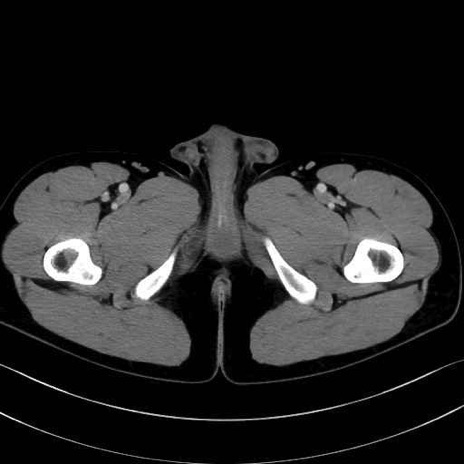

大腿方形筋 (Quadratus femoris)